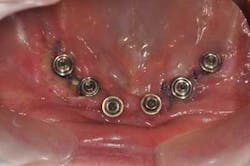

Mandibular arch: the lower jaw is fully edentulous. Initially, according to the patient, an implant-supported five-unit bridge (23 to 27) was made on four implants (Alphabio®) placed in 2007. Tooth 22 was present at the time and a removable partial denture replaced the bilateral posterior missing teeth.

Then, in January 2012, tooth 22 was extracted and a second implant specialist placed a new implant (Zimmer Dental®) to replace it. The GP decided to use a Locator® attachment system on this new implant and have the existing denture stabilized over it, without paying any attention to the collapsing situation of the upper right.Fig. 3: CT scan shows the existing implants positions and the bone volume available

Fig. 11: For a better prosthetic outcome, the implants in site 26 and 27 have been extracted and replaced with two Biomet 3i® implants.